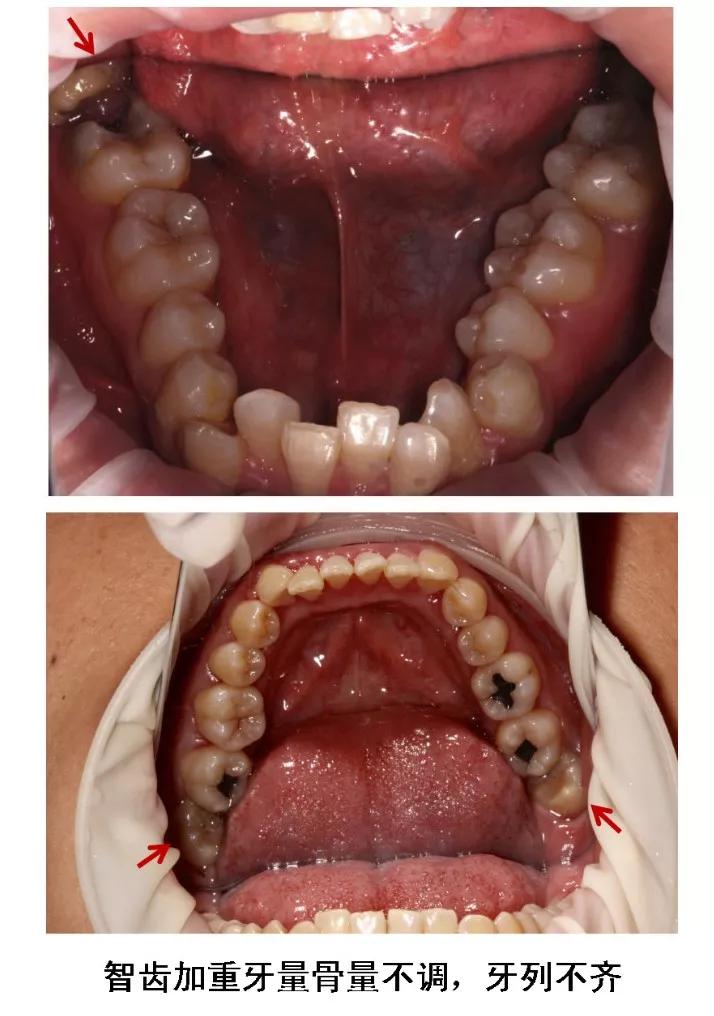

6、牙齿需要矫正,以及在12-16岁做过矫正的小朋友,需要根据正畸医生的建议,及时拔除智齿,以获得完美的牙列和脸型!

图片来源:作者提供